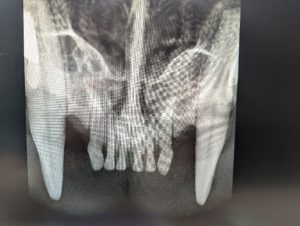

As you can see above, the incisors of this cat on the left are fully intact, with no signs of fracture or resorption. On the right, however, the incisors have snapped leaving the roots intact but invisible above the gum line.